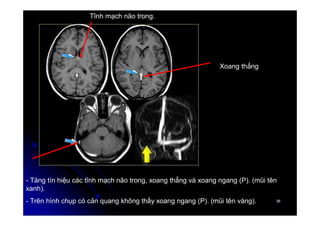

- Tăng tín hiệu các tĩnh mạch não trong, xoang thẳng và xoang ngang (P). (mũi tên

xanh).

- Trên hình chụp có cản quang không thấy xoang ngang (P). (mũi tên vàng).

Xoang thẳng

Tĩnh mạch não trong.